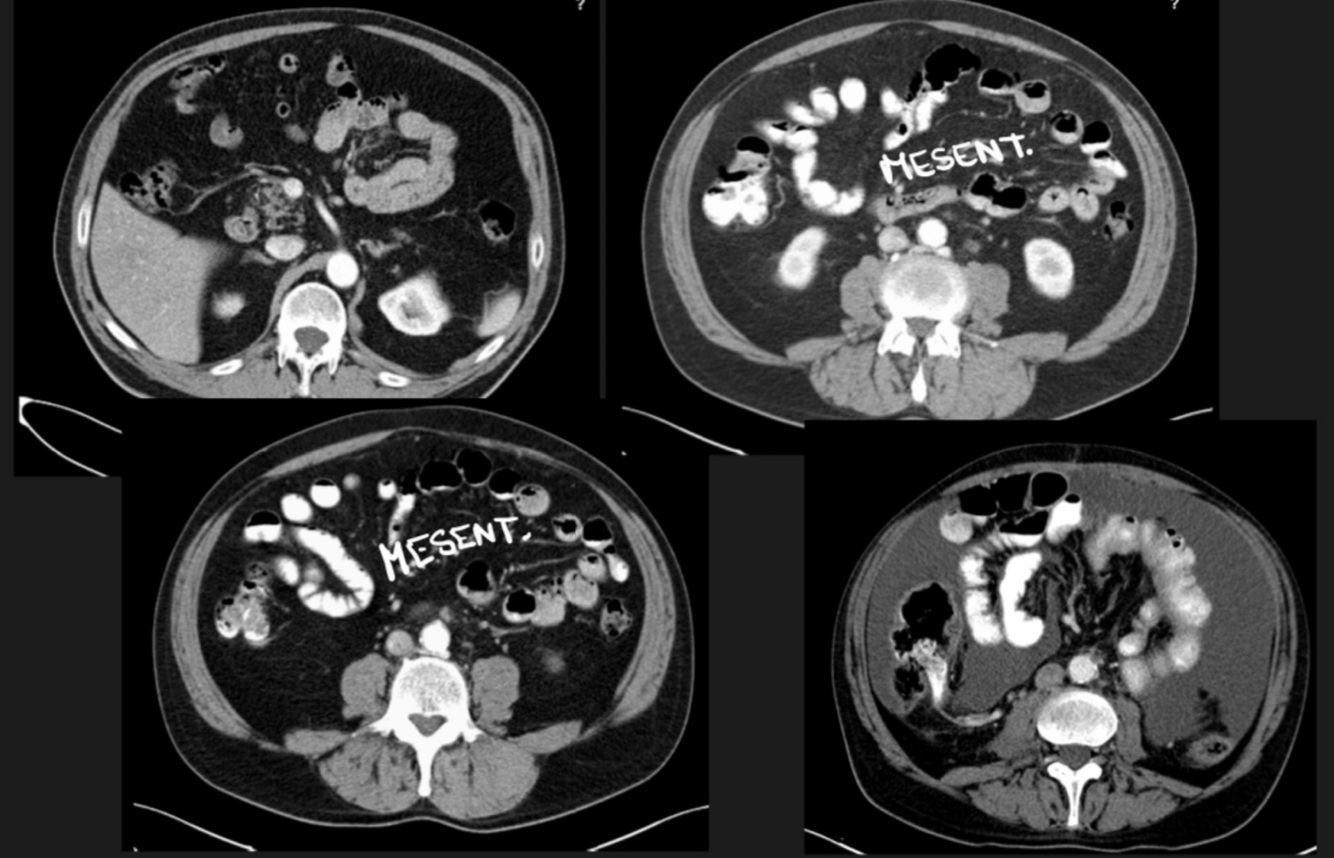

… divided the peritoneal cavity in two.

A

Transverse mesocolon (mesentery of colon)

11

Q

In the supramesocolic region, we find…

Liver, stomach and spleen